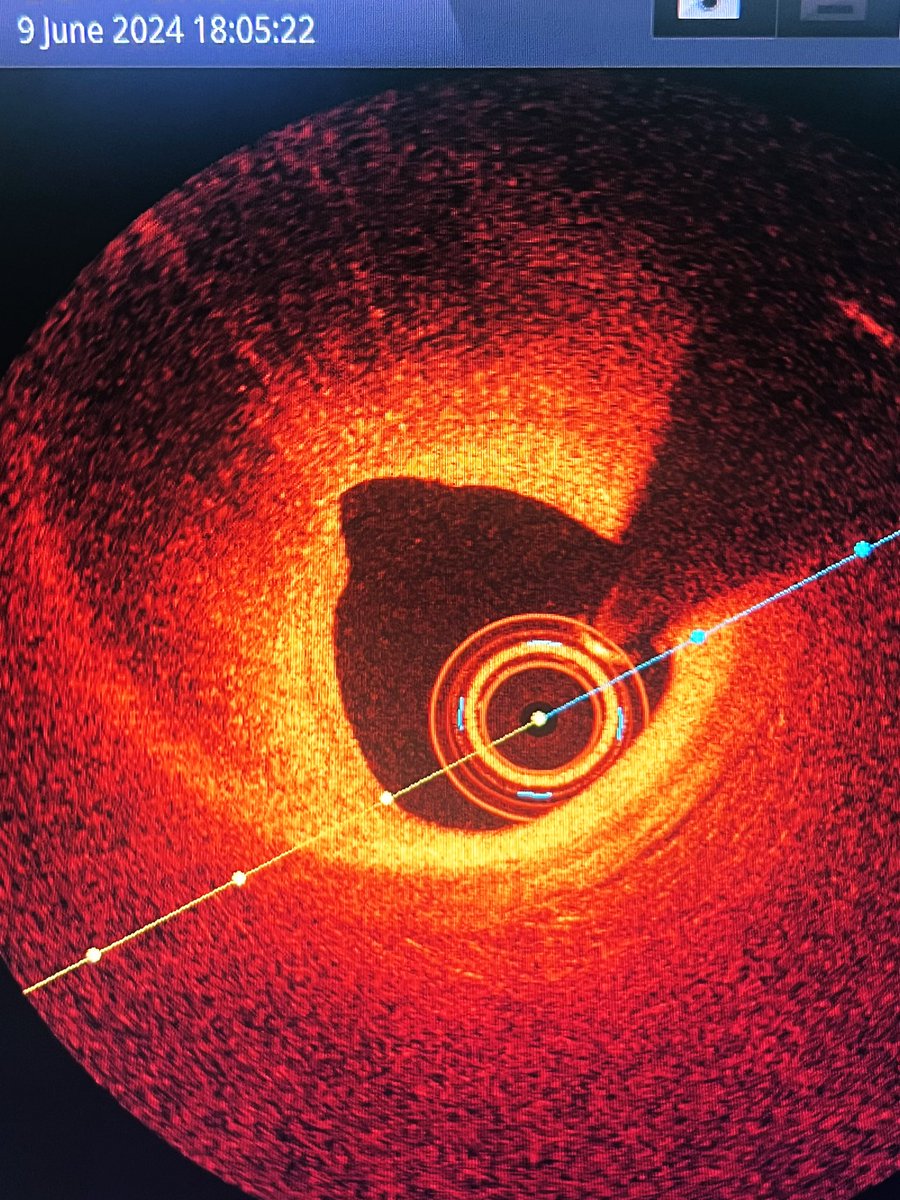

A 63 y.o female presented with NSTEMI. One year before CTA with normal LAD/RCA and mild lesion in OM1. Here is the angio and OCT images. What would you do?